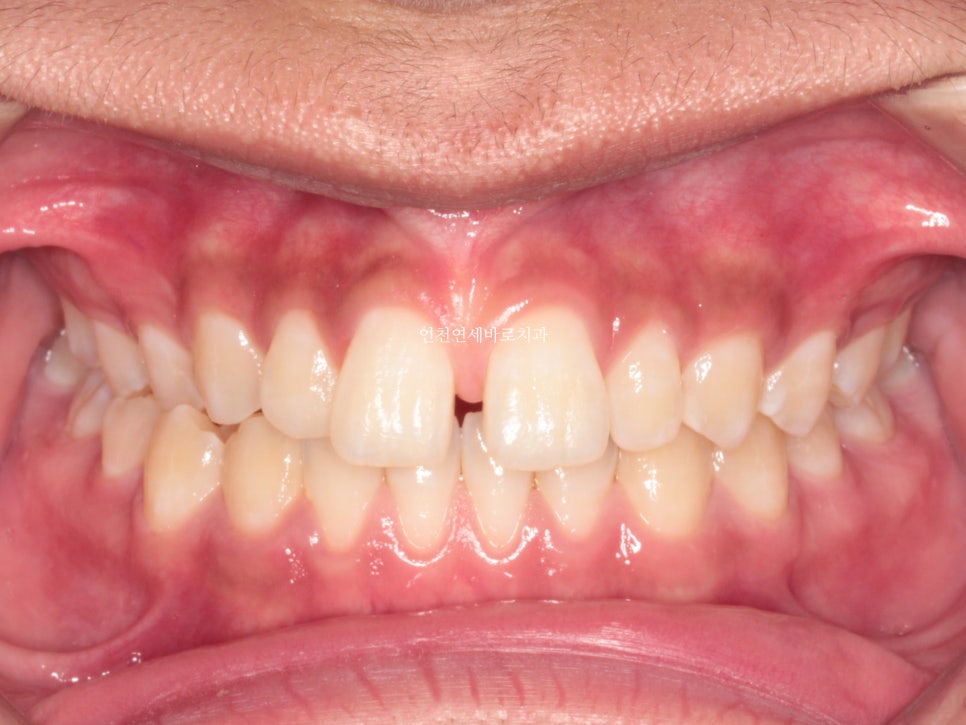

치료 받으러 온 고1 남학생입니다.

앞니가 벌어진 것도 문제였지만

화살표쪽에 보이는 반대교합도 문제였습니다.

한번의 재제작을 했던 환자분입니다.

재제작 소요기간 한달을 포함해서 환자분이 병원에 오고 딱 1년만에 치료가 마무리 되었습니다.

문제가 되었던 오른쪽 어금니 교합도 좋게 마무리 하였습니다.

악궁확장장치는 사용하지 않았습니다.